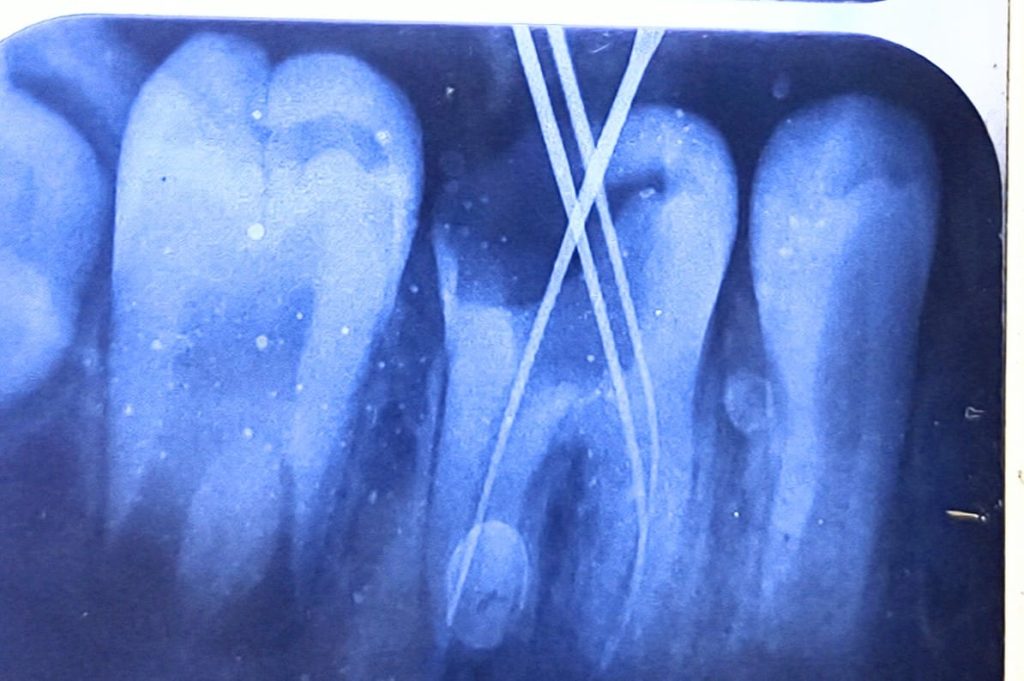

Formacresol pulpotomy till cervical constriction followed by placing calcium hydroxide as pulp capping agent for apex formation to occur naturally. sealed the tooth with temporary restoration and put the patient on 6 months follow up.

after another 6 months the tooth show complete apex formation and patient had no pain, did the root canal treatment, and packed with composite.